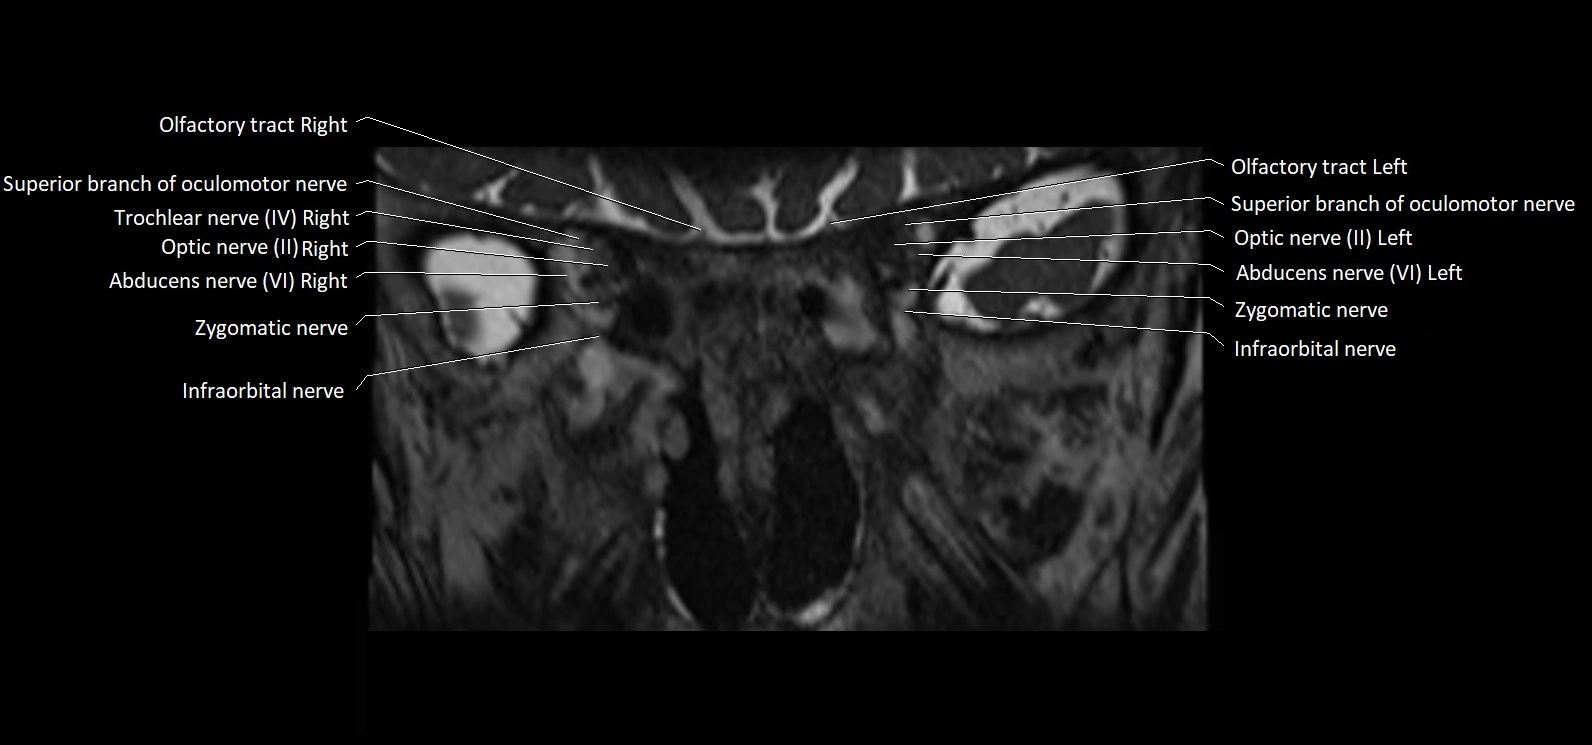

MRI Appearance

• The abducens nerve is a small, thin, linear structure

• Best visualized on high-resolution T2-weighted 3D MRI sequences (e.g., FIESTA or CISS)

• Seen as a hypointense (dark) line running from the brainstem at the pontomedullary junction, traversing the prepontine cistern, and entering Dorello’s canal under the petrosphenoidal ligament, then into the cavernous sinus, and finally the orbit

• May be challenging to visualize in standard MRI due to its small size

• Pathology may be inferred by absence, displacement, or enhancement of the nerve

MRI images

image